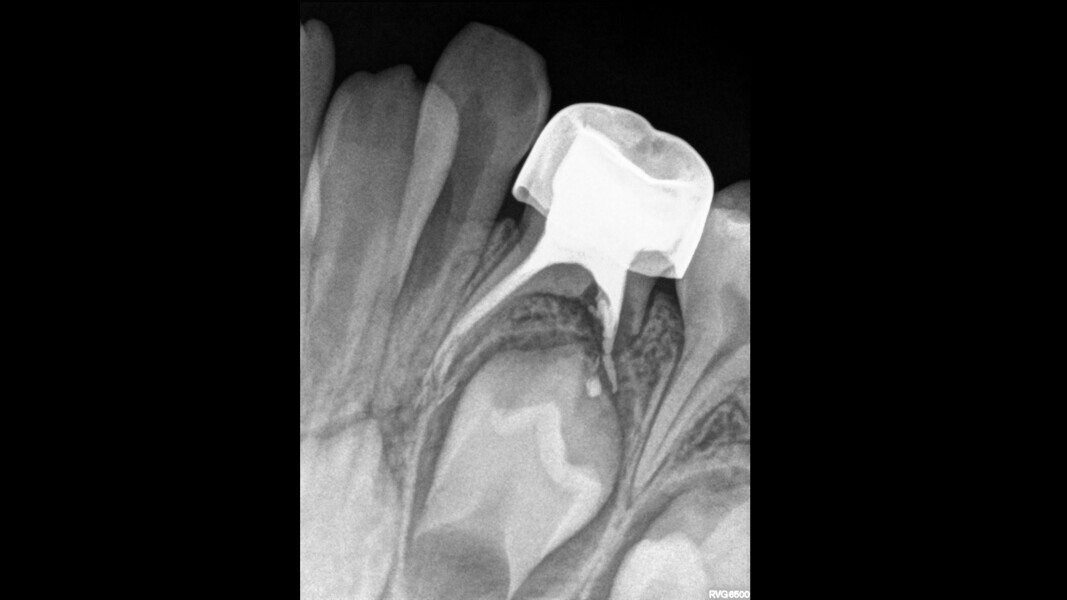

This male patient was 5 years and 8 months old and presented with distal deep interproximal caries on a maxillary left first primary molar and an associated buccal sinus tract. The patient was asymptomatic and without a history of pain. Pulp necrosis with suppurative periapical periodontitis was diagnosed. Three canals were located and prepared for obturation. Apical over-extrusion with the ZOE was observed. Fifteen days later, the patient was asymptomatic and the sinus tract had resolved, so the decision was made to restore the tooth with a stainless-steel crown. Follow-up after 30 months showed periapical healing of the mesial apical radiolucency and no signs or symptoms of disease or pain.